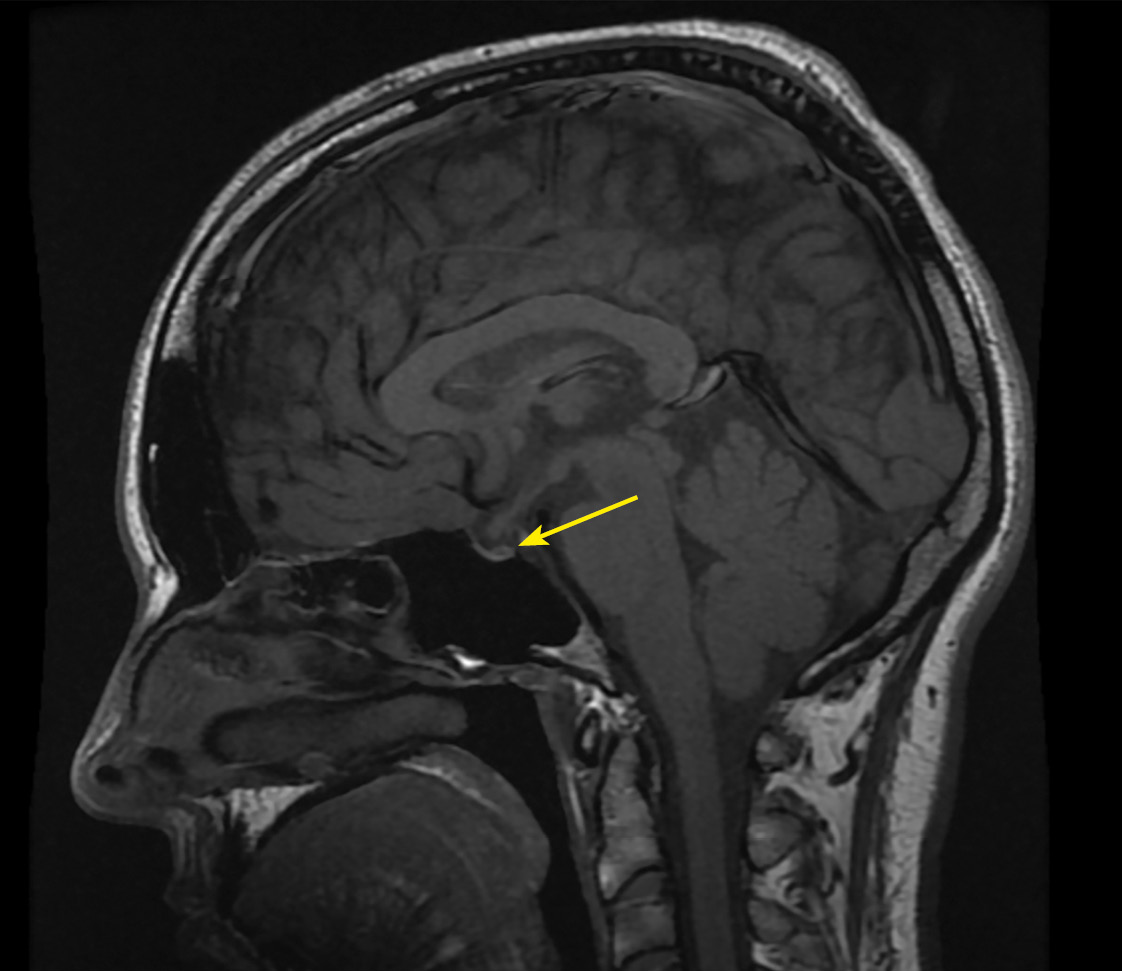

По данным МРТ головного мозга с контрастным усилением: МР-картина частично «пустого» турецкого седла, отсутствие сигнала от нейрогипофиза. Таким образом, подтвержден центральный генез сохраняющегося несахарного диабета (рис. 5, 6).

Рисунок 5. МРТ головы с контрастным усилением, Т1-взвешенное изображение,

коронарная (фронтальная) проекция. МР-картина частично «пустого» турецкого седла.

Рисунок 6. МРТ головы с контрастным усилением, Т1-взвешенное изображение,

сагиттальная проекция. МР-картина частично «пустого» турецкого седла.

Отсутствие сигнала от нейрогипофиза (изменения указаны стрелкой).